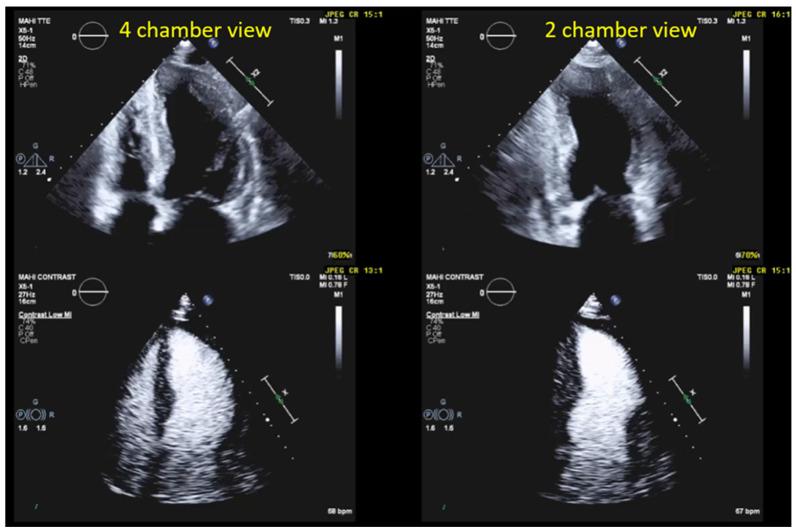

How to Perform Cardiac Contrast-Enhanced Ultrasound (cCEUS): Part I.

Ultrasound enhancing agents (UEAs, formerly called contrast agents) for assessments of the left heart have improved the applicability of echocardiography and the accuracy of echocardiographic measurements. UEAs have been recommended for several diagnostic echocardiographic procedures by national and supernational agencies. The increased use of UEAs during the last years provided more evidence and experience in clinical practice data which is helpful for optimizing the UEA procedures and which will be useful for both newcomers to UEA in echocardiography and sonographers/physicians with experience in echocardiography with UEAs. In two parts, this review focuses on the "how to do" for the approved UEA applications. This is part 1, covering the available UEAs and providing specific guidance on the assessment of global and regional LV function. Part 2 covers the imaging of myocardial disease and masses as well as myocardial perfusion. Recommendations include the application of UEAs in two-dimensional echocardiography as there is limited data on three-dimensional echocardiography. A step-by-step approach is proposed for each of the procedures as well as guidance on how to interpret recordings and how to report them.